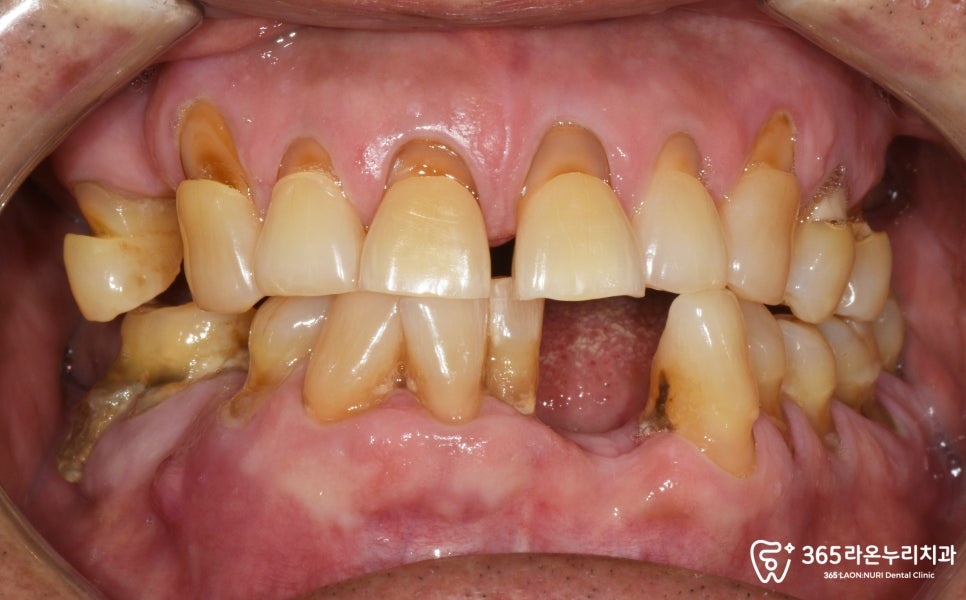

왼쪽 아래 앞니가 하나 결손되어 있는 것이

먼저 관찰되며, 다른 치아들도

흔들리고 상태가 좋지 않았습니다.

특히, 결손된 앞니 부위의

골도 심하게 내려가 있었습니다.

위턱 양쪽의 어금니가 모두 사라졌고,

오른쪽의 경우 작은 어금니 하나가

없는 모습입니다.

반대편에 있는 작은 어금니 하나도 심하게

파절되어, 코어 + 크라운을

진행해드리기로 결정했습니다.

아래턱 역시도, 치조골이 많이

내려가게 되면서 치아 뿌리쪽이

많이 드러나고 있었습니다.